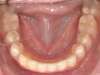

Cas 5 : Description

Absence congénitale des incisives latérales supérieures. Appareils fixes pour créer l’espace nécessaire à la mise en place de facettes en remplacement des latérales.

Après